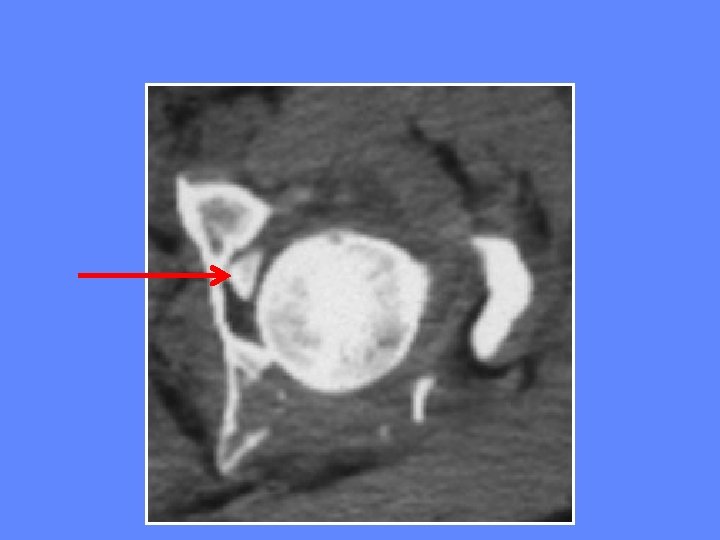

Incarcération d’un fragment intra-articulaire